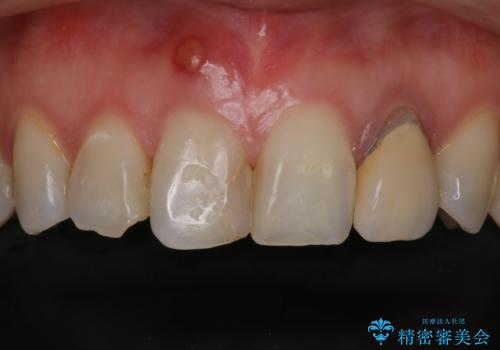

- 患者様は前歯にできものができたということで来院されました。

歯髄診断を行い、失活していると判断して根管治療を行いました。